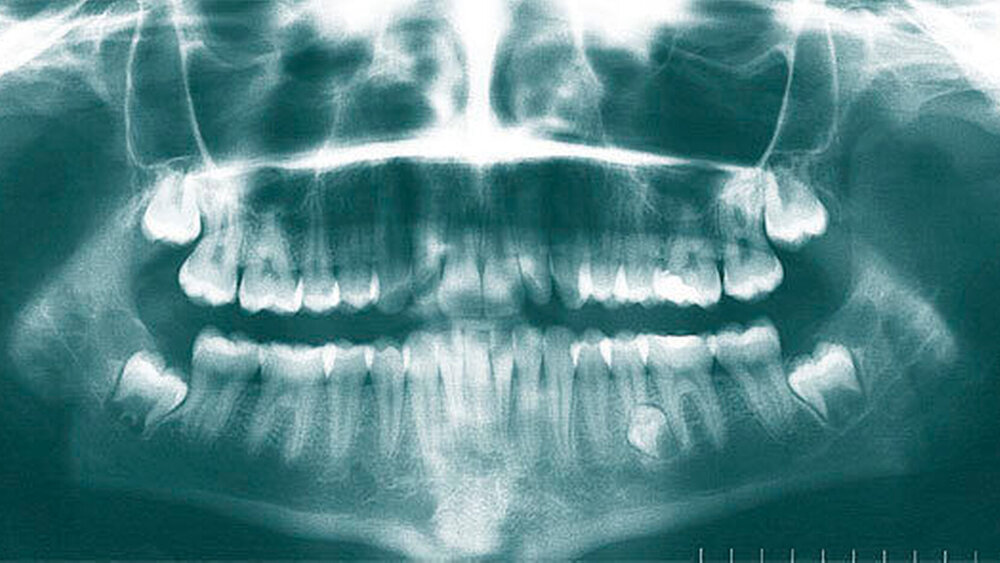

Überzählige Zähne werden nach ihrer Lage im Zahnbogen und auch aufgrund ihrer Morphologie eingeteilt. Basierend auf der Lage unterscheidet man bei überzähligen Zähnen zwischen Mesiodens (Oberkiefer median), zwischen den zentralen Inzisiven (Abbildungen 5 und 6), einem zusätzlichen Schneidezahn (zentral oder lateral), Eckzahn, Prämolar (Abbildung 7), Paramolar und Distomolar (Abbildungen 8). Mesiodentes werden am häufigsten dia- gnostiziert, wobei Prozentsätze zwischen 38,8 Prozent bis 86,3 Prozent der überzähligen Zähne in der Literatur zu finden sind [Salcido-García et al., 2004/38,8 Prozent, Fernández Montenegro et al., 2006 /46.9 Prozent; Mossaz et al., 2014/48.5 Prozent; Ferrés-Padró et al., 2009/53.2 Prozent; Schmuckli et al., 2010/75 Prozent; Rajab Hamdan 2002/83.2 Prozent; Liu et al., 2007/86.3 Prozent]. Überzählige Prämolaren und seitliche Schneidezähne sind die zweithäufigste Gruppe der überzähligen Zähne. Überzählige Eckzähne, Paramolaren und Distomolaren dagegen gelten als eher selten [Rajab Hamdan, 2002; Salcido- García et al., 2004; Liu et al., 2007; Ferrés-Padró et al., 2009; Schmuckli et al., 2010; Mossaz et al., 2014]. Einzig eine Spanische Gruppe [Fernández Montenegro et. al., 2006] berichtete, dass Paramolaren und Distomolaren insgesamt relativ häufig seien (18 Prozent, beziehungsweise 5,6 Prozent). Überzählige Zähne kommen im Ober- und Unterkiefer vor, wobei sich überzählige Schneidezähne in der Regel im Oberkiefer, überzählige Prämolaren sich dagegen eher im Unterkiefer befinden [Fernández Montenegro et al., 2006; Ferrés-Padró et al., 2009; Mossaz et al., 2014]. Überzählige Molaren wiederum treten normalerweise im Oberkiefer auf [Cassetta et al., 2014; Kaya et al., 2014].